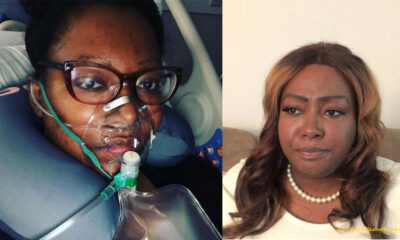

Mom Forced to Choose Between Cancer Treatments and Childbirth Makes Her Decision

After losing both his love and his newborn son within months of each other, the man...